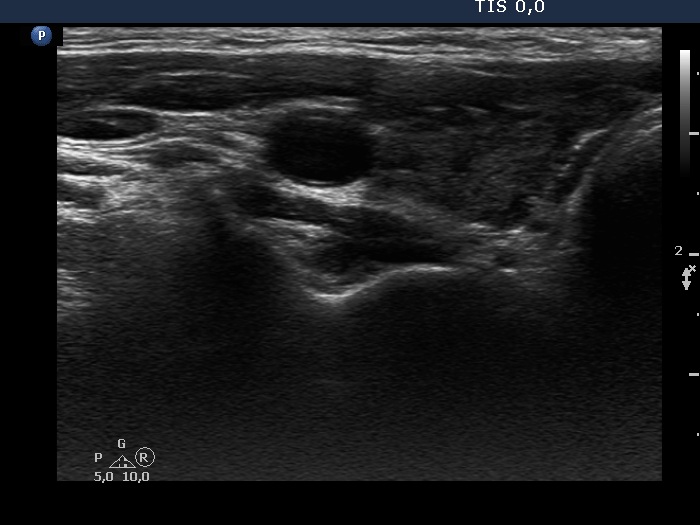

Discrete lesion or nodule in Hashimoto's thyroiditis - case 11 (1241) (ultrasonographic picture 2)

Middle part of the right lobe, transverse view.